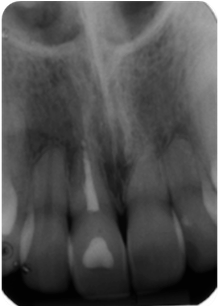

Tooth Injury comprises a group of clinical conditions that can have the separation or breakage of the tooth and its surrounding tissues. A case of multiple concomitant dental trauma is reported. In 2004, a female patient, 11 years old, visited the dental office a half hour after a dental trauma caused by a fall in the pool. She complained of mild discomfort in the tooth 11; in a clinical analysis, it was partially displaced from its socket and showed grade 2 mobility; in a radiographic analysis, the tooth showed an increase in the periodontal ligament space, a diagnosis of extrusive luxation. The adjacent teeth 21 and 22, presented subgingival bleeding, diagnosed with subluxation. After preparing the treatment plan, clinical approach consisted of manual reduction of the tooth 11 and non-rigid splint of affected teeth. The patient received a prescription of antibiotic and anti-inflammatory. After 15 days, the splint was removed and the teeth 11, 21 and 22 showed pulpal sensibility, maintaining the same results for 4 months. In the 4th month, tooth 11 was diagnosed with pulp necrosis, thus requiring endodontic treatment. After 10 years, teeth were asymptomatic, with a slight color change in tooth 11; the cone beam scan indicated root resorption in the apical third of the three elements and the presence of dystrophic calcification of teeth 21 and 22. In conclusion, the injured teeth remain in function with relevant follow-up period, highlighting the search for a response, upon the purpose of the study.